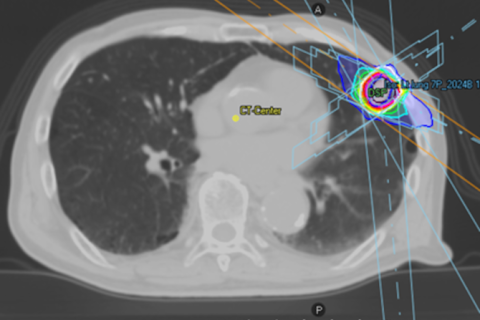

肺がんに対する定位放射線治療(肺がんのピンポイント治療)

当院の放射線治療装置(Vero4DRT)は、肺がんに対する定位放射線治療(ピンポイント照射)を得意としています。定位放射線治療は、病変を正確にとらえ、多方向から1点に向けて放射線を集中して照射する治療法です。

周囲の正常な肺への影響をできるだけ抑えることができるため、副作用が少ない治療とされています。実際に、治療中や治療後に自覚症状がほとんどみられない方も多くいらっしゃいます。

肺がんに対する定位放射線治療の適応は、大きさがおおよそ5cm以下(できれば3cm以下)で、リンパ節転移のない肺がんとなります。

放射線治療は、1回あたり約20分程度で、腫瘍の場所や大きさに応じて4回から8回行います。治療期間中の副作用は少なく、外来通院で治療を受けていただくことが可能です。

肺がんに対する定位放射線治療

肺がんに対する放射線治療(多方向からのビームの配置)